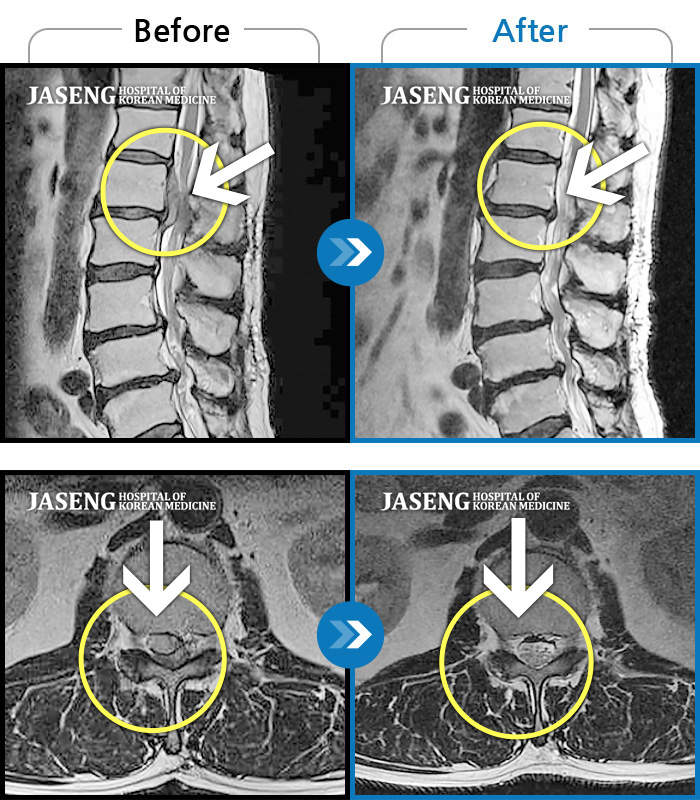

허리디스크

수원 · 김태성 원장

허리 통증과 좌측 대퇴부 저림과 당김

촬영시기

2023.02.03 ~ 2024.02.14

2024.11.21